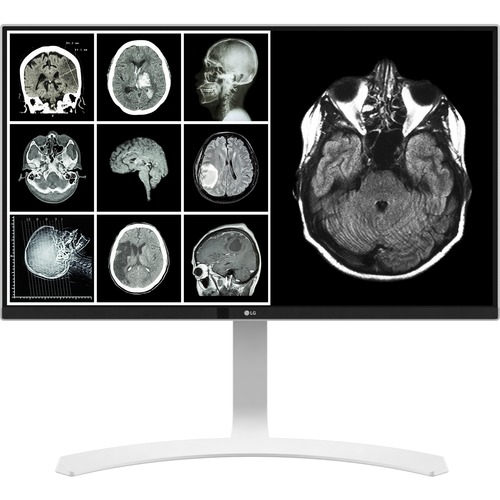

LG 27HJ712C-W – 27″ 8MP Clinical Monitor

SKU:

27HJ712C-W

LG 27HJ713C-B – 27″ 8MP Clinical Monitor

SKU:

27HJ713C-B